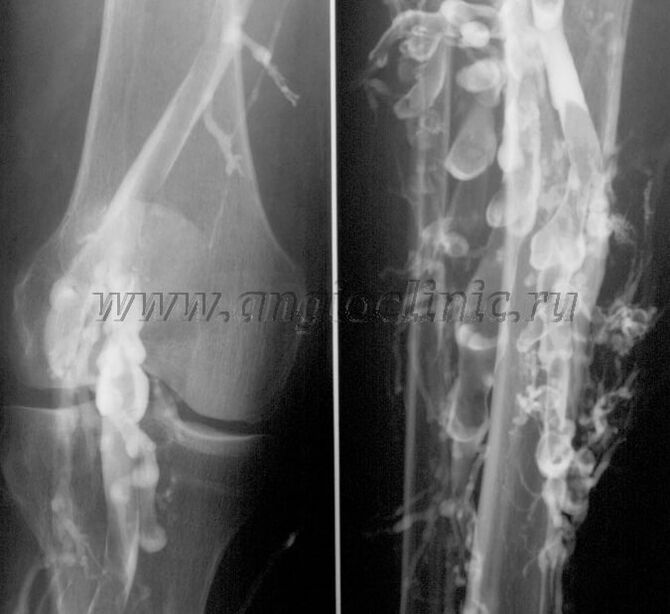

Контраст венография

Адатта, веноздук патологияны толук диагностикалоо үчүн УЗИ сканерлөө жетиштүү, бирок кээ бир учурларда терең жана үстүнкү веноздук системанын абалынын ортосундагы байланышты изилдөө зарыл, айрыкча варикоздун жана орто варикоздун рецидивинде.

Бул көйгөйлөрдү чечүү үчүн, контраст рентген изилдөө колдонулат. Сафеноздук веналар тешип, контраст колдонулат. Рентген аппаратынын мониторунда контрасттын кыймылы байкалып, бардык зарыл сыноолор жана проекциялар жүргүзүлөт. Учурда варикоздук веналардын венографиясы өтө сейрек колдонулат.